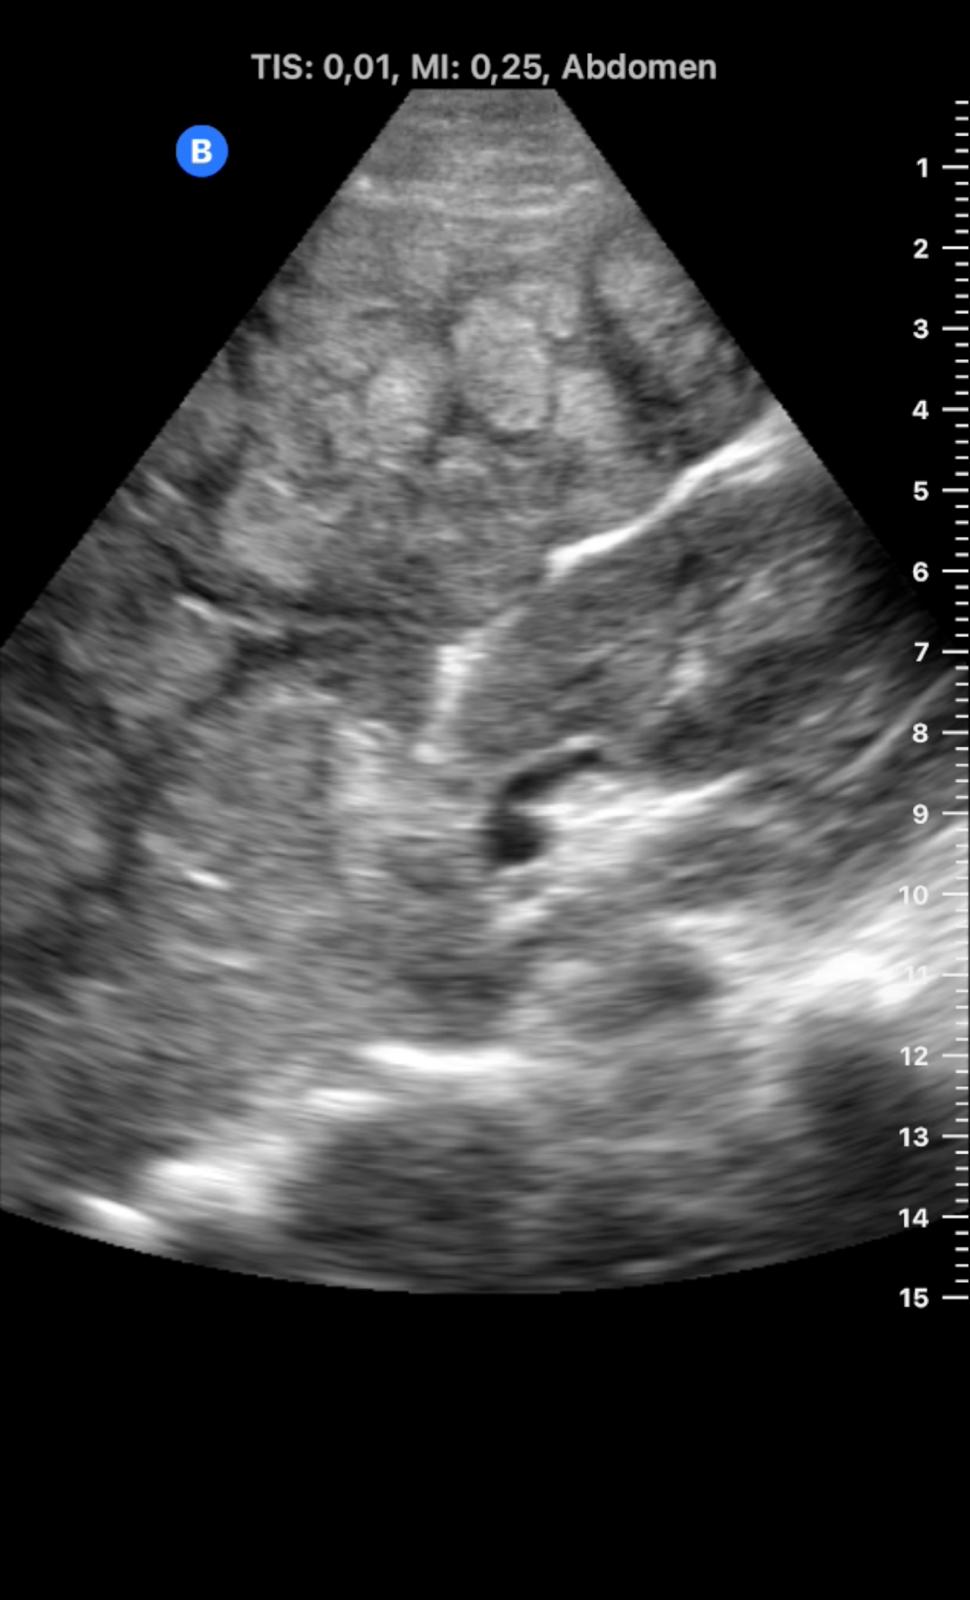

En ecografía en Centro de Salud: La práctica totalidad del parénquima hepático se encuentra sustituida por múltiples lesiones sólidas nodulares hiperecoicas, de predominio en el lóbulo hepático derecho, donde presentan tendencia a la confluencia y conforman una masa que alcanza los 13 cm de diámetro máximo. La vena porta es permeable y ectásica, con esplenomegalia. Ambos son signos de hipertensión portal.